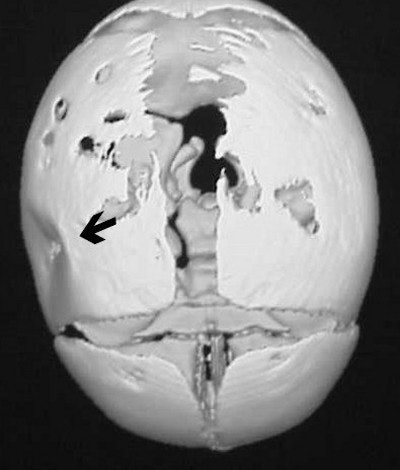

Three-dimensional reconstructed images in surface-shaded volume rendering show an obvious breech of the skull in the affected area (figures CT 7 and CT 8). Detectives matched the defect to a pair of the father’s cowboy boots. He was charged and convicted of beating his wife during the pregnancy.

![]() |

| Figure CT 7 |